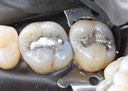

Mark Chun #2 & 3 pre-op

Mark Chun #2 & 3 amalgam removal

Mark Chun #2 & 3 caries removal